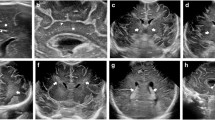

Elastography is a US technique that allows tissue stiffness to be assessed via studying the altered propagation of sound waves. Elastography in general can be categorized into strain and shear wave elastography, the former using internal (i.e. carotid pulsation, physiological respiration) or external compression stimuli for semi-automated quantification of tissue stiffness and the latter using US-generated shear-wave stimuli for quantitation of tissue stiffness. Normal developmental evolution of the gray and white matter elasticity has been shown in infants [130, 131], suggestive of its potential role as an imaging biomarker of neurodevelopment and developmental delay. Regional variations in elasticity have also been shown in preterm and term infants, with highest-to-lowest elasticity (or lowest-to-highest stiffness) brain regions in the following order: periventricular white matter, subcortical white matter and caudate [131, 132]. The alterations in brain tissue stiffness have correlated with pathological processes in preterm infants. Initial reports of shear-wave elastography in an infant with profound hypoxic–ischemic injury demonstrated more than a two-fold increase in tissue stiffness of the cortex, likely in the setting of critically elevated intracranial pressure (Figs. 23 and 24) [133, 134]. Since then, a prospective trial has applied shear-wave elastography in 166 infants (110 healthy and 56 with hydrocephalus) and reported a modest (r=0.69, P<0.001) correlation between brain elasticity and intracranial pressure in neonatal hydrocephalus [135].

Brain elastography. Brain sagittal US elastography in an 8-day-old preterm boy (born at 33 weeks’ gestation) shows normal periventricular white matter with normal stiffness of 0.94±0.15 m/s. Image modified from [134], with permission

Brain elastography after anoxia. Brain sagittal US elastography in a 6-month-old (born at 37 weeks’ gestation; gender unknown) with severe anoxia. Imaging demonstrates elevated values in the gray and white matter of 3.6±0.21 m/s at 30 min after return of spontaneous circulation. Image modified from [134], with permission